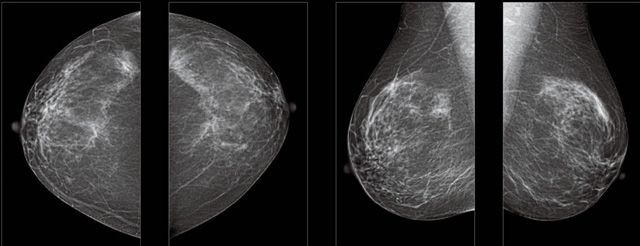

首先不同年齡階段的乳腺篩查頻次種類不一樣。青春期女性第二性征明顯發(fā)育開始,每個月進行自我乳腺檢查。20-30歲的女性就不推薦進行乳腺檢查,因為年輕女性的乳腺組織非常緊急。鉬靶X光線等檢查的射線不能辨別腫塊跟腺體。身體就白吸收了輻射,影響了身體健康。每個月自檢一次就是在洗澡時候,對著鏡子看看乳房外觀正常,皮膚潰爛、腫塊、顏色改變、再摸一下有沒小疙瘩。乳腺高危人群,特別是有乳腺CA遺傳傾向的女性,乳腺導管跟小葉不典型增生,原位癌。30歲前有乳房放療的女性。乳腺癌篩查可以把年齡提前到40歲前。40到70歲的女性可以在適合的機會篩查。

采用影像檢查技術來發(fā)現(xiàn)疑似特定病檢查跟人群的普查。一到兩年進行一次X光線的乳腺檢查。記過是C或者D型,可以加上B超協(xié)同。還可以一年一次核磁共振MRI檢查。70歲以上的女性認為絕經(jīng)的女性是比較安全的。實際上也有乳腺癌的風險。65歲以上風險也很大。也是需要進行機會性篩查。